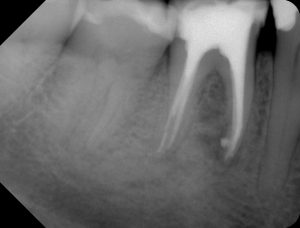

Hier ein Zahn 46 mit zwei Wurzeln und zwei distalen respektive vier mesialen Kanälen.

46 WF orthograde Röntgenaufnahme

46 WF mesialexzentrische Röngtenaufnahme